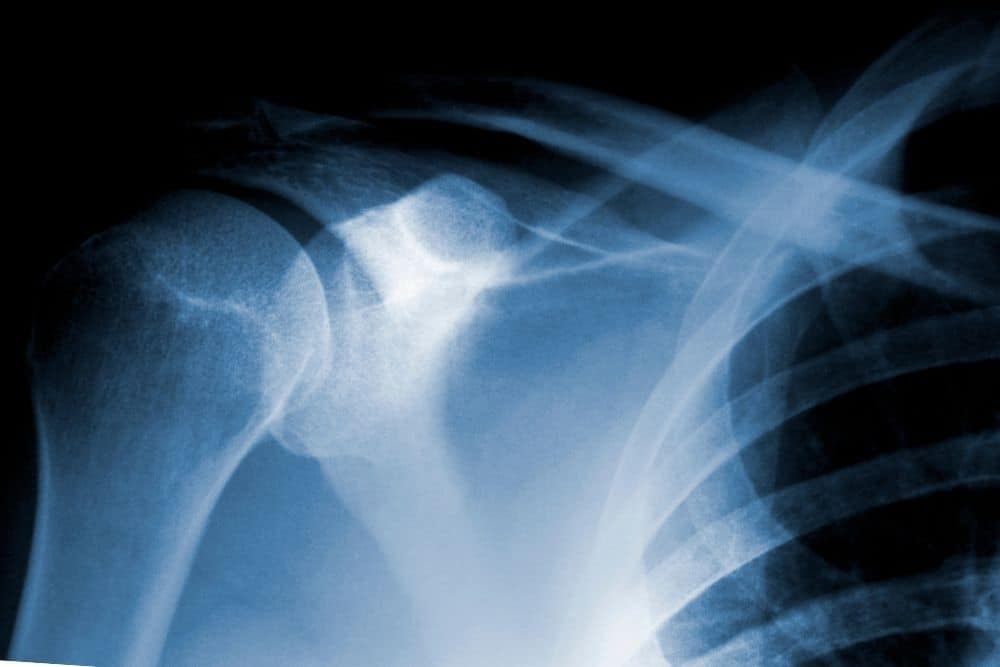

El diagnóstico se realiza mediante una exploración clínica acompañada de pruebas de imagen. La radiografía de hombro es la más utilizada, ya que permite identificar los depósitos de calcio. En algunos casos se recurre a la ecografía o la resonancia para valorar el grado de afectación del tendón y descartar lesiones asociadas en el manguito rotador.